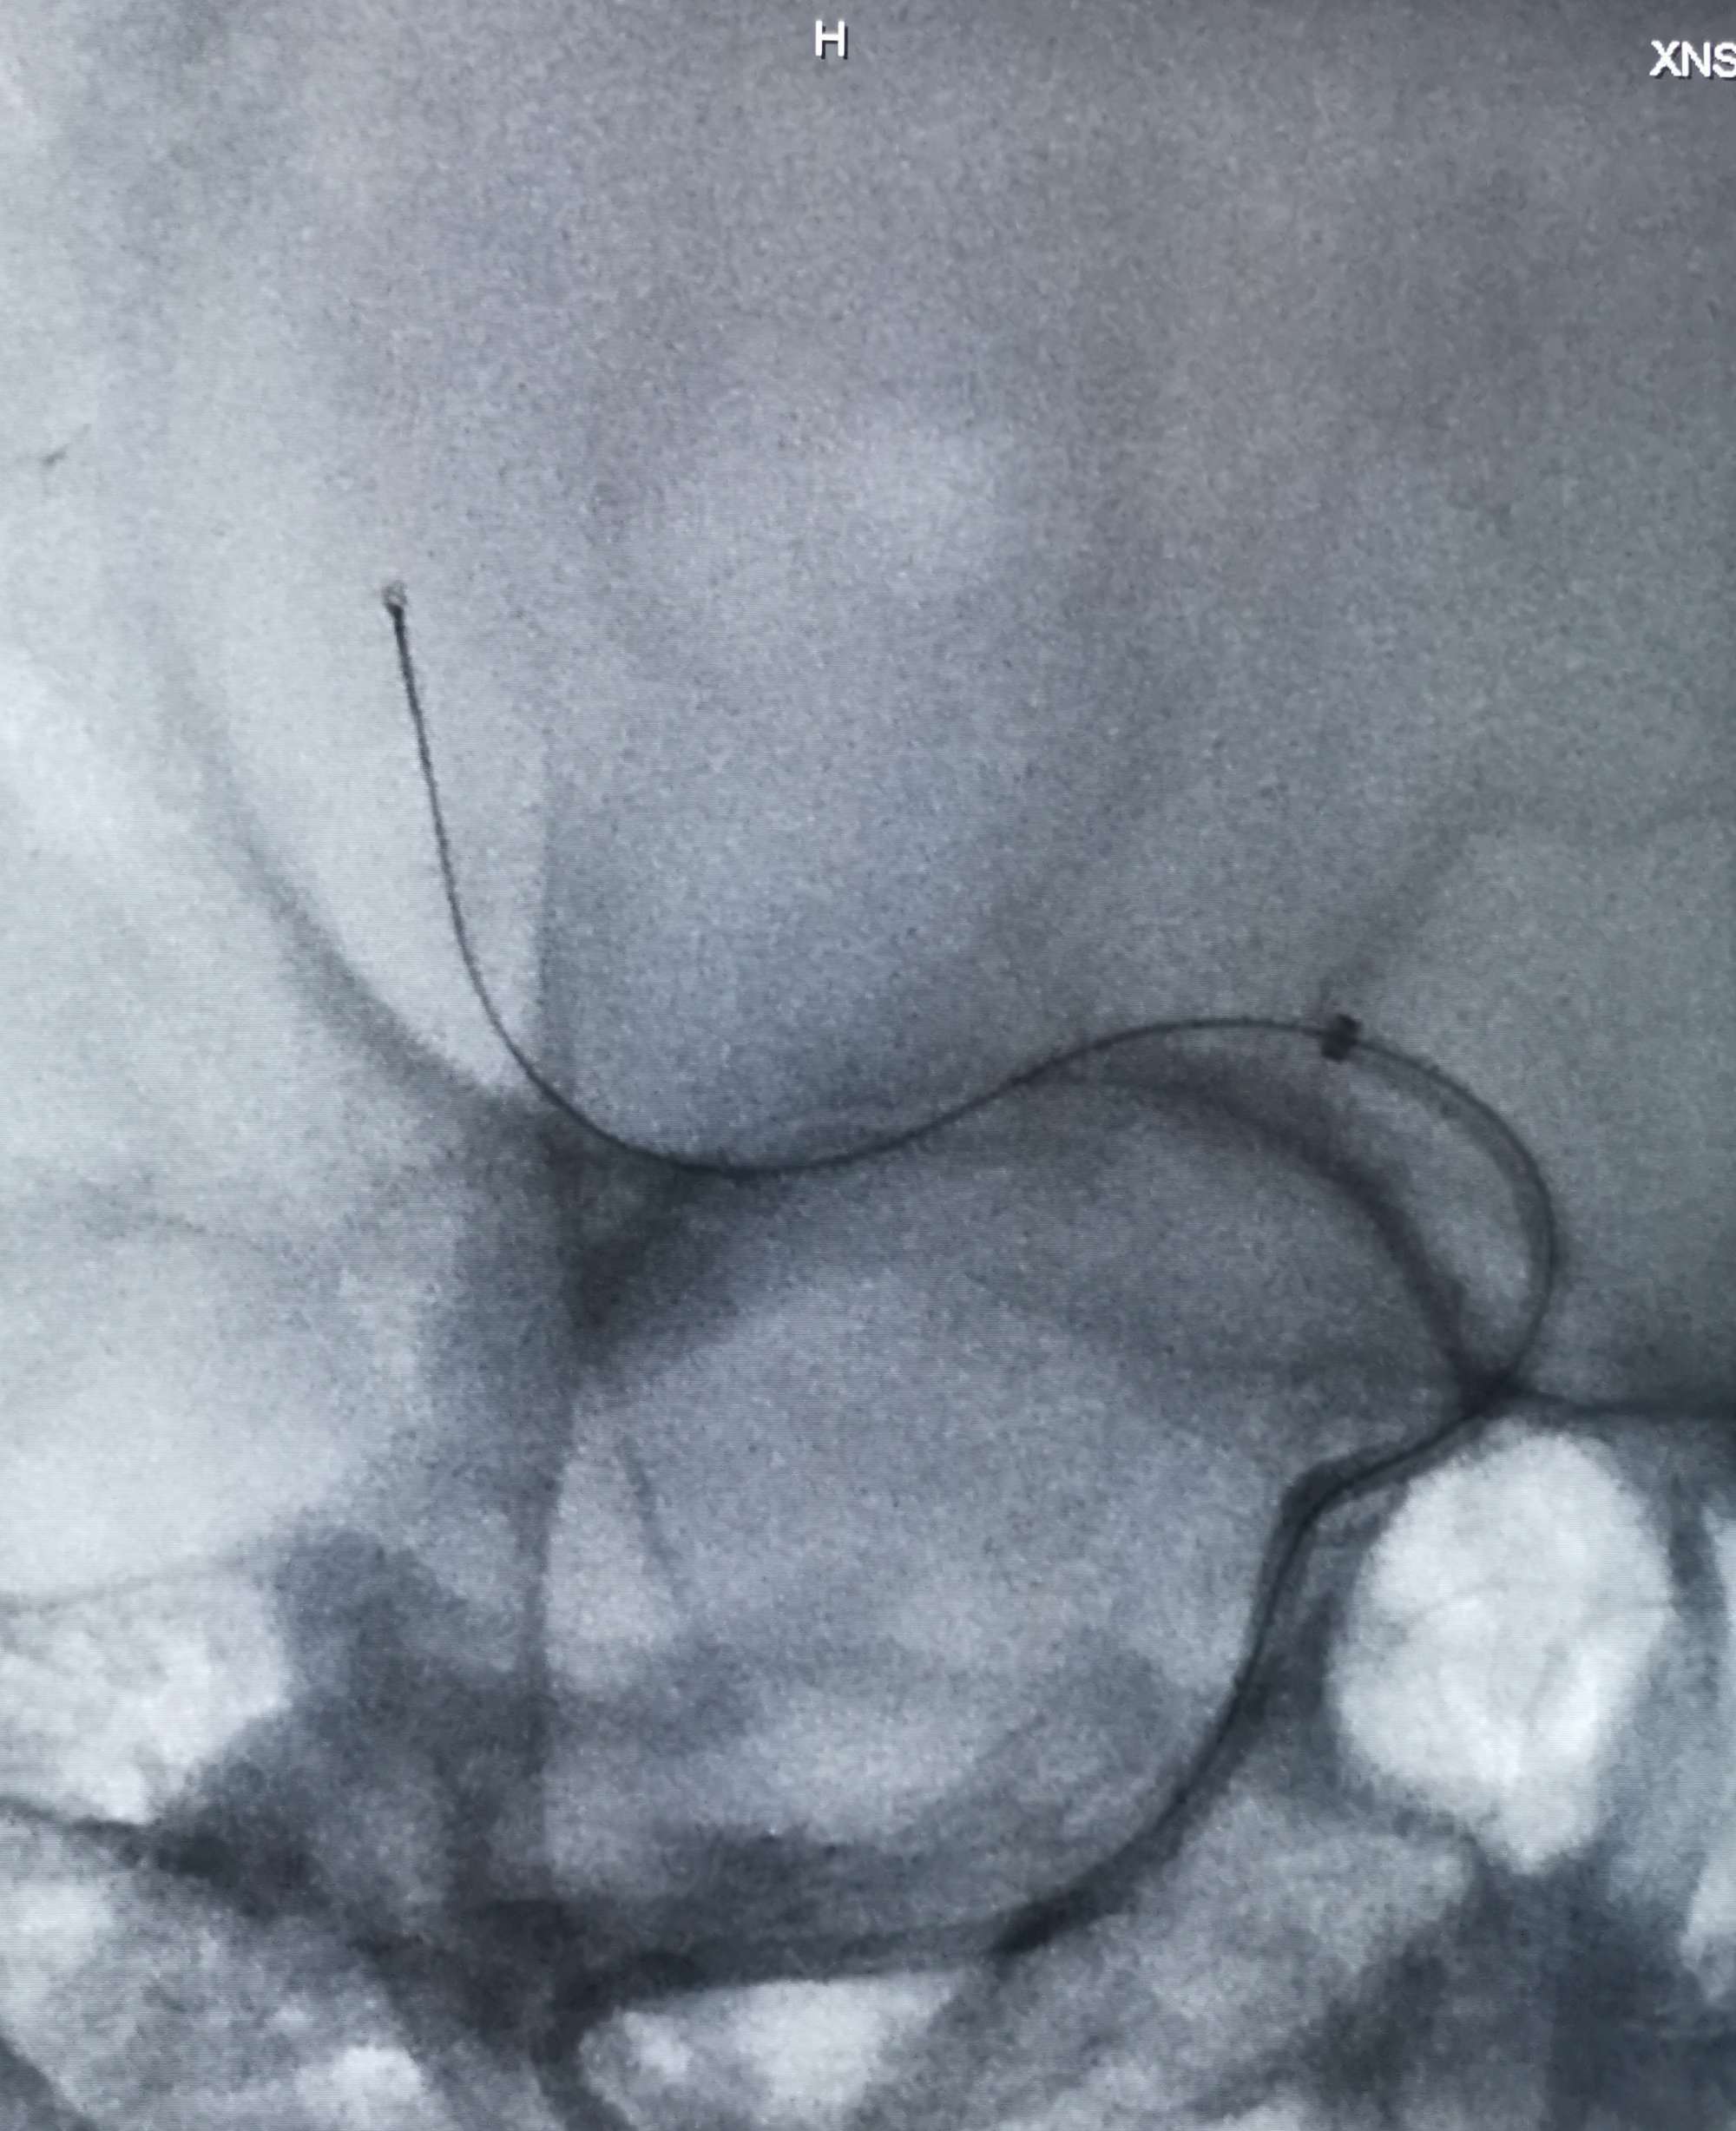

微导管在微导丝引导下通过血栓段